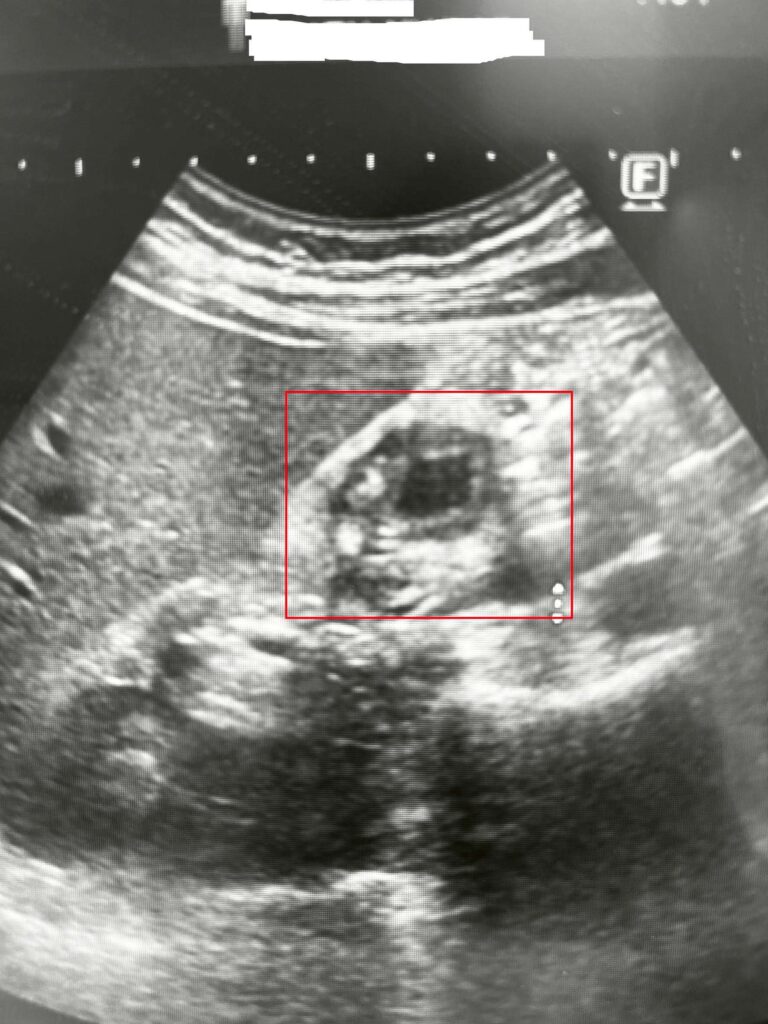

圖1說:49歲男子因心窩悶痛與右上腹脹痛,五年來四處求醫,近期至博田國際醫院肝膽胰外科看診並接受檢查時,才被發現罹患「膽囊腺肌症」。(博田國際醫院)

主治醫師李金德教授表示,膽囊腺肌症屬於良性病變,但因膽囊內皮細胞與平滑肌層過度增生,使膽囊壁出現不均勻肥厚,甚至合併膽結石,有時超音波能看到類似小囊腔的影像,往往讓初期診斷難度增加。林先生多年來飯後加劇的上腹悶脹、噁心與背部放射痛的症狀,與一般膽結石極為相似,呈現「症狀明顯,但沒有任何結石」的矛盾現象,因此屢屢被認為是胃部問題或輕微膽囊發炎。

膽囊腺肌症的影像表現其實分成不同型態:有些病灶只侷限於膽囊底部,屬於「局部型」,常在其他檢查中偶然被發現;另一類則出現在膽囊體部,形成明顯的壁層收縮,稱為「節段型」,此型態因與文獻中較高的膽囊癌風險相關,在臨床上特別受到重視;還有一部分患者屬於「廣泛型」,整個膽囊壁都呈現全面性肥厚,容易掩蓋早期惡性變化,使影像判讀更加複雜。正因為三種類型的分佈部位不同、臨床意義也不同,影像醫學的細膩觀察成了確診關鍵。